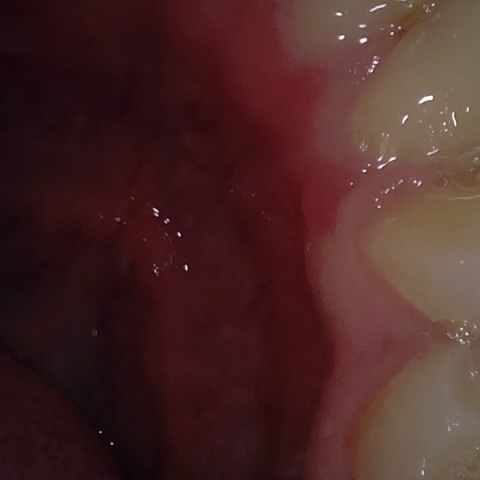

Annotated as "Bad"